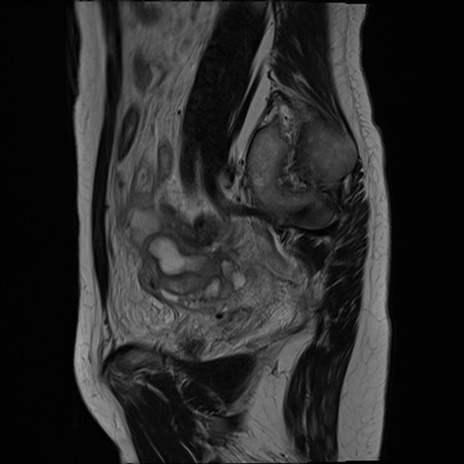

症例39 T2WI(矢状断像)

MRI(4日後)